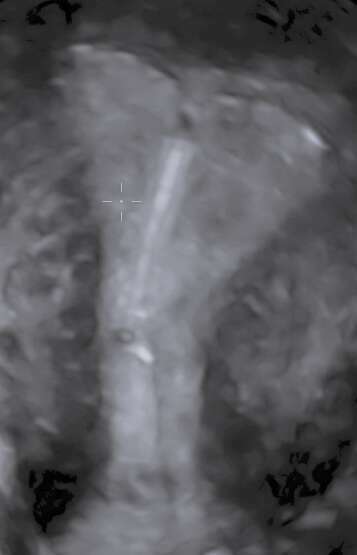

- L'échographie de datation

- Les 3 échographies recommandées pendant la grossesse du 1er, 2ème et 3ème trimestre.

- Les échographies de croissance et/ou de surveillance du col, de contrôle de présentation, sur indication médicale.

- Les échographies de grossesses gémellaires de suivi simple, 1er, 2ème, 3ème trimestre et croissances.